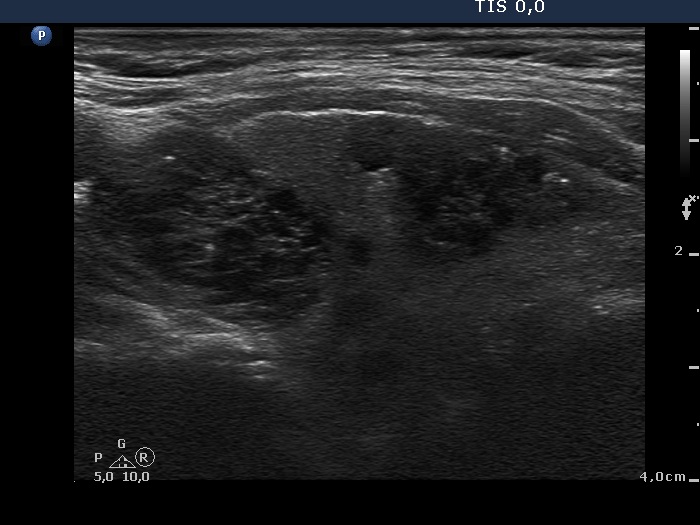

Ultrasonography. The right thyroid was significantly enlarged and contained multiple nodules with different echogenicity. The left thyroid was decreased in size and presented small insignificant lesions.

Scintigraphy disclosed an autonomously functioning nodule with a maximal diameter of 5 cm in the right lobe.

The cytological pattern is characteristic of hyperthyroidism. The sonographic presentation is characteristic of a toxic multinodular goiter because of the shrinkage of the contralateral lobe caused by the low TSH level.